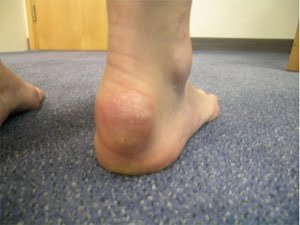

Insertional Achilles Tendonitis

Insertional Achilles tendonitis occurs at the point where the tendon attaches to the heel bone (calcaneus). This type of tendonitis is often seen in older individuals and may have different causes, pathology, imaging techniques, and treatment options compared to non-insertional Achilles tendonitis.

Pathology of Insertional Achilles Tendonitis

Insertional Achilles tendonitis involves inflammation and degeneration of the tendon fibers near the point of attachment to the heel bone. This can lead to bone changes and the development of bone spurs.